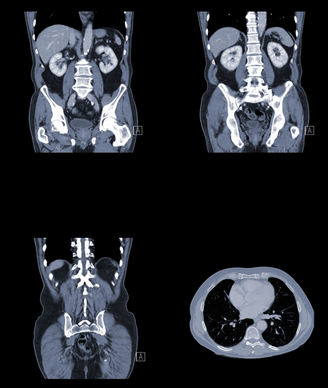

A 62-year-old man presents with anemia and fever. A renal mass is detected and a biopsy is performed. What is your diagnosis?